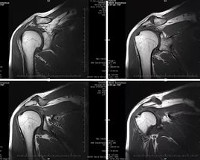

КТ плечевого сустава является методом выбора в очевидных сложных клинических случаях. Альтернативные методы, используемые при обследовании плечевого сустава, включают рентгенографию, ультразвуковое исследование и артроскопию. Рентгенография - самый распространенный и самый дешевый метод визуализации, характеризующийся меньшим количеством информации и более высокой дозой облучения по сравнению с КТ. Ультразвук не означает, что пациент подвергается облучению, он позволяет изучать структуру сустава в реальном времени и в разных плоскостях. Его недостатками являются зависимость информативности процедуры от подготовки врача, а также от анатомо-физиологических особенностей организма пациента. МРТ более отчетливо обнажает мягкие ткани - связки, сухожилия, суставную капсулу, мышцы, не требует рентгеновских лучей. При диагностике патологии костей возможности МРТ и УЗИ ограничены. Артроскопия, в отличие от КТ, является инвазивной процедурой и может сочетаться с хирургическим лечением.

Компьютерная томография плечевого сустава может выявить нарушения структурной целостности костей, соответствующих трещинам или переломам, а также смещение поверхностей суставов относительно друг друга, что является неполным или полным сигналом дислокации. Согласно одному исследованию, остеопороз, деформация, сужение суставного пространства, анкилоз - симптомы артрита и остеоартроза, а также скопление крови или гноя в суставной полости - проявления гемартроза, абсцесса. При увеличении контраста можно обнаружить наличие неоваскуляризации при новообразованиях, что определяет степень злокачественности опухоли. На контрастных изображениях видна деформация сосуда или его «перелом» - проявления тромбоза, эмболии, атеросклероза.